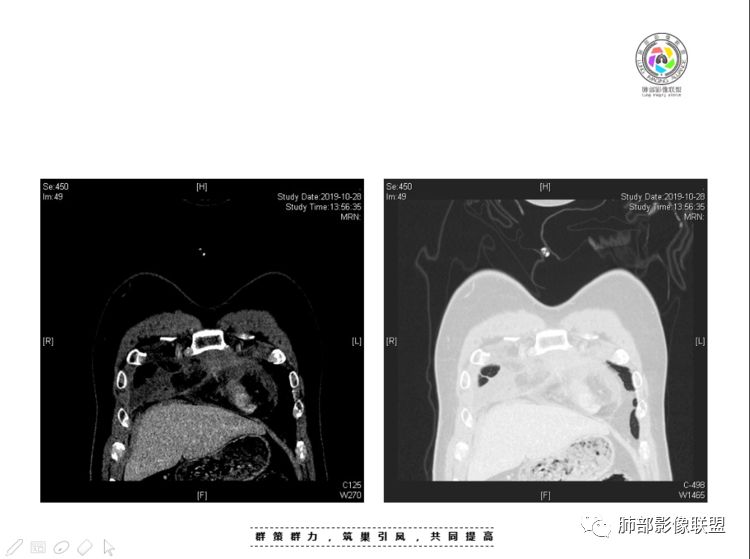

2、前纵隔内病灶囊实性混杂密度病灶,囊性病灶主要位于右侧,张力较高,有分隔影,囊壁右侧缘光整,病灶左侧实性部分边界不清明显强化,病灶肺瘤交界面大部分边界清楚,部分模糊。

胸腺瘤/胸腺癌符合吗?

胸腺瘤/胸腺癌:病灶内那么大的囊,常规考虑B型以上胸腺瘤,囊内有分隔影,病灶周围脂肪间隙模糊,常规考虑侵袭性胸腺瘤或胸腺癌,若侵袭性胸腺瘤,常侵犯胸膜、心包,很少累及肺。胸腺癌易侵犯胸膜、肺并纵隔淋巴结及远处转移。但肺内腺癌形态更符合原发灶。胸膜及叶间裂转移则即可来自肺,也可来自胸腺癌。